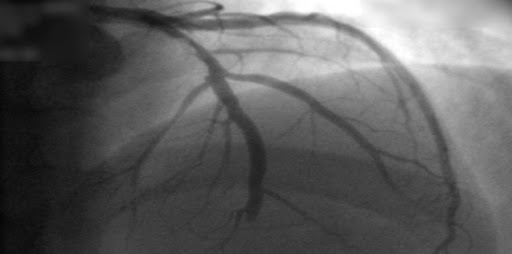

Estudios coronarios en la cardiopatía isquémica estable: ¿TC o cateterismo?

Este estudio no encontró diferencia entre mujeres y varones en el beneficio del uso de la tomografía computarizada (TC) en lugar de la angiografía coronaria invasiva como prueba diagnóstica inicial para el manejo del dolor torácico estable en pacientes con una probabilidad previa a la prueba intermedia de enfermedad arterial coronaria. La TC inicial se asoció con menos complicaciones importantes relacionadas con el procedimiento en las mujeres y una frecuencia más baja del compuesto MACE expandido en los hombres.British Medical Journal, 19 de octubre de 2022.